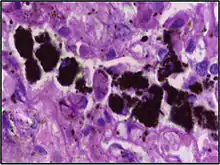

Alveolar macrophages are frequently seen to contain granules of exogenous material such as particulate carbon that they have picked up from respiratory surfaces. Such black granules may be especially common in smoker's lungs or long-term city dwellers.

Comparison of pigmented pulmonary macrophages

Disease | Macrophage name | Macrophage pigment appearance (HE stain) | Usual macrophage location | Associated medical history | Image | Image comment |

---|---|---|---|---|---|---|

Anthracosis | Black-brown granules | Interstitium (perivascular) | ![]() |

Black arrow shows interstitial anthracotic pigment. Nearby macrophages (white arrow) can be presumed to contain anthracotic pigment. | ||

Respiratory bronchiolitis | "Smoker’s macrophages" | Yellow to light brown and finely granular[4] | Airways (especially respiratory bronchioles) | Tobacco smoking | ![]() |

Smoker's macrophage in center |

Chronic pulmonary congestion | Siderophages | Brown-golden and refractile.[5] | Alveoli[6] |

|

![]() |

Siderophage (black arrow), and interstitium with edema, hemosiderin deposition (black arrow) and collagenous thickening, indicating heart failure. |